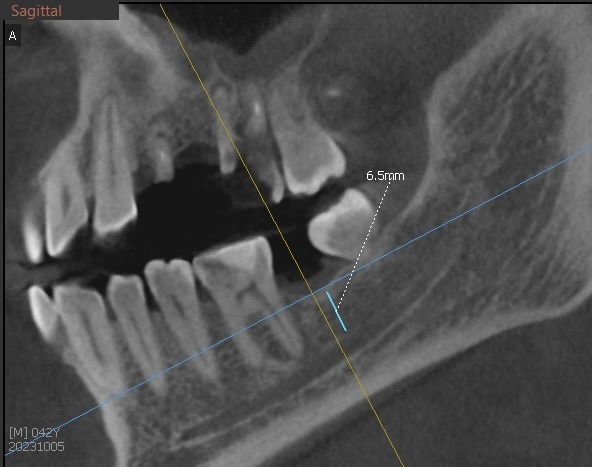

В нашем случае имеем 7-8 миллиметров до нерва (на скрине поменьше данные, но это в самом "тонком" месте):

До нижнечелюстного канала мало кости

Для стандартного имплантата - маловато будет.